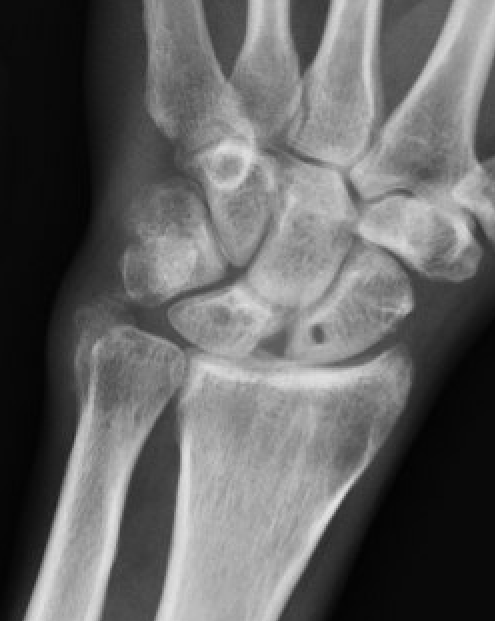

X-ray

Scapholunate gap > 3 mm

AP

| Terry Thomas sign | Cortical ring sign | Scaphoid shortened |

|---|---|---|

|

Increased scapholunate interval > 3 mm compared with other side |

End on view of distal scaphoid due to flexion | Shortened due to flexion |